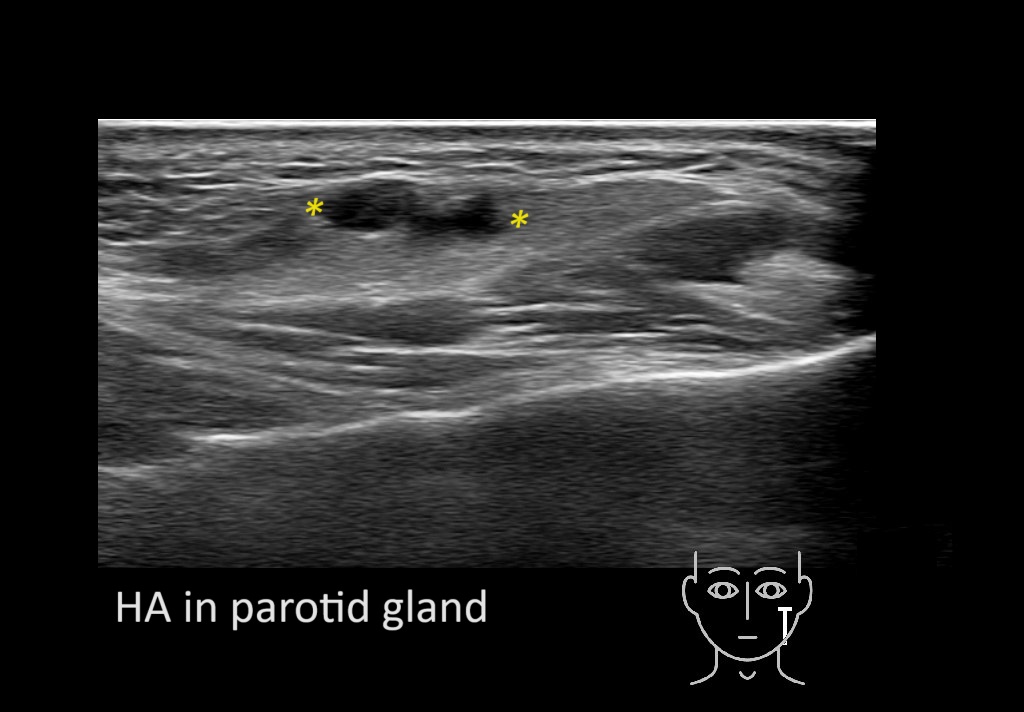

Filler injections in the parotid gland may go unnoticed, however, inflammatory reactions and abscesses may occur. Hypervascularity can be seen with color doppler. Filler deposits are supposed to be injected into the superficial fatty layer . The space to inject into this layer may be limited. Routinely we measure a width of 2-4 millimeters with sometimes subcutaneous layers being less than one millimeter thick.

Hover over an image to view the secondary image or click on the image title for more information.